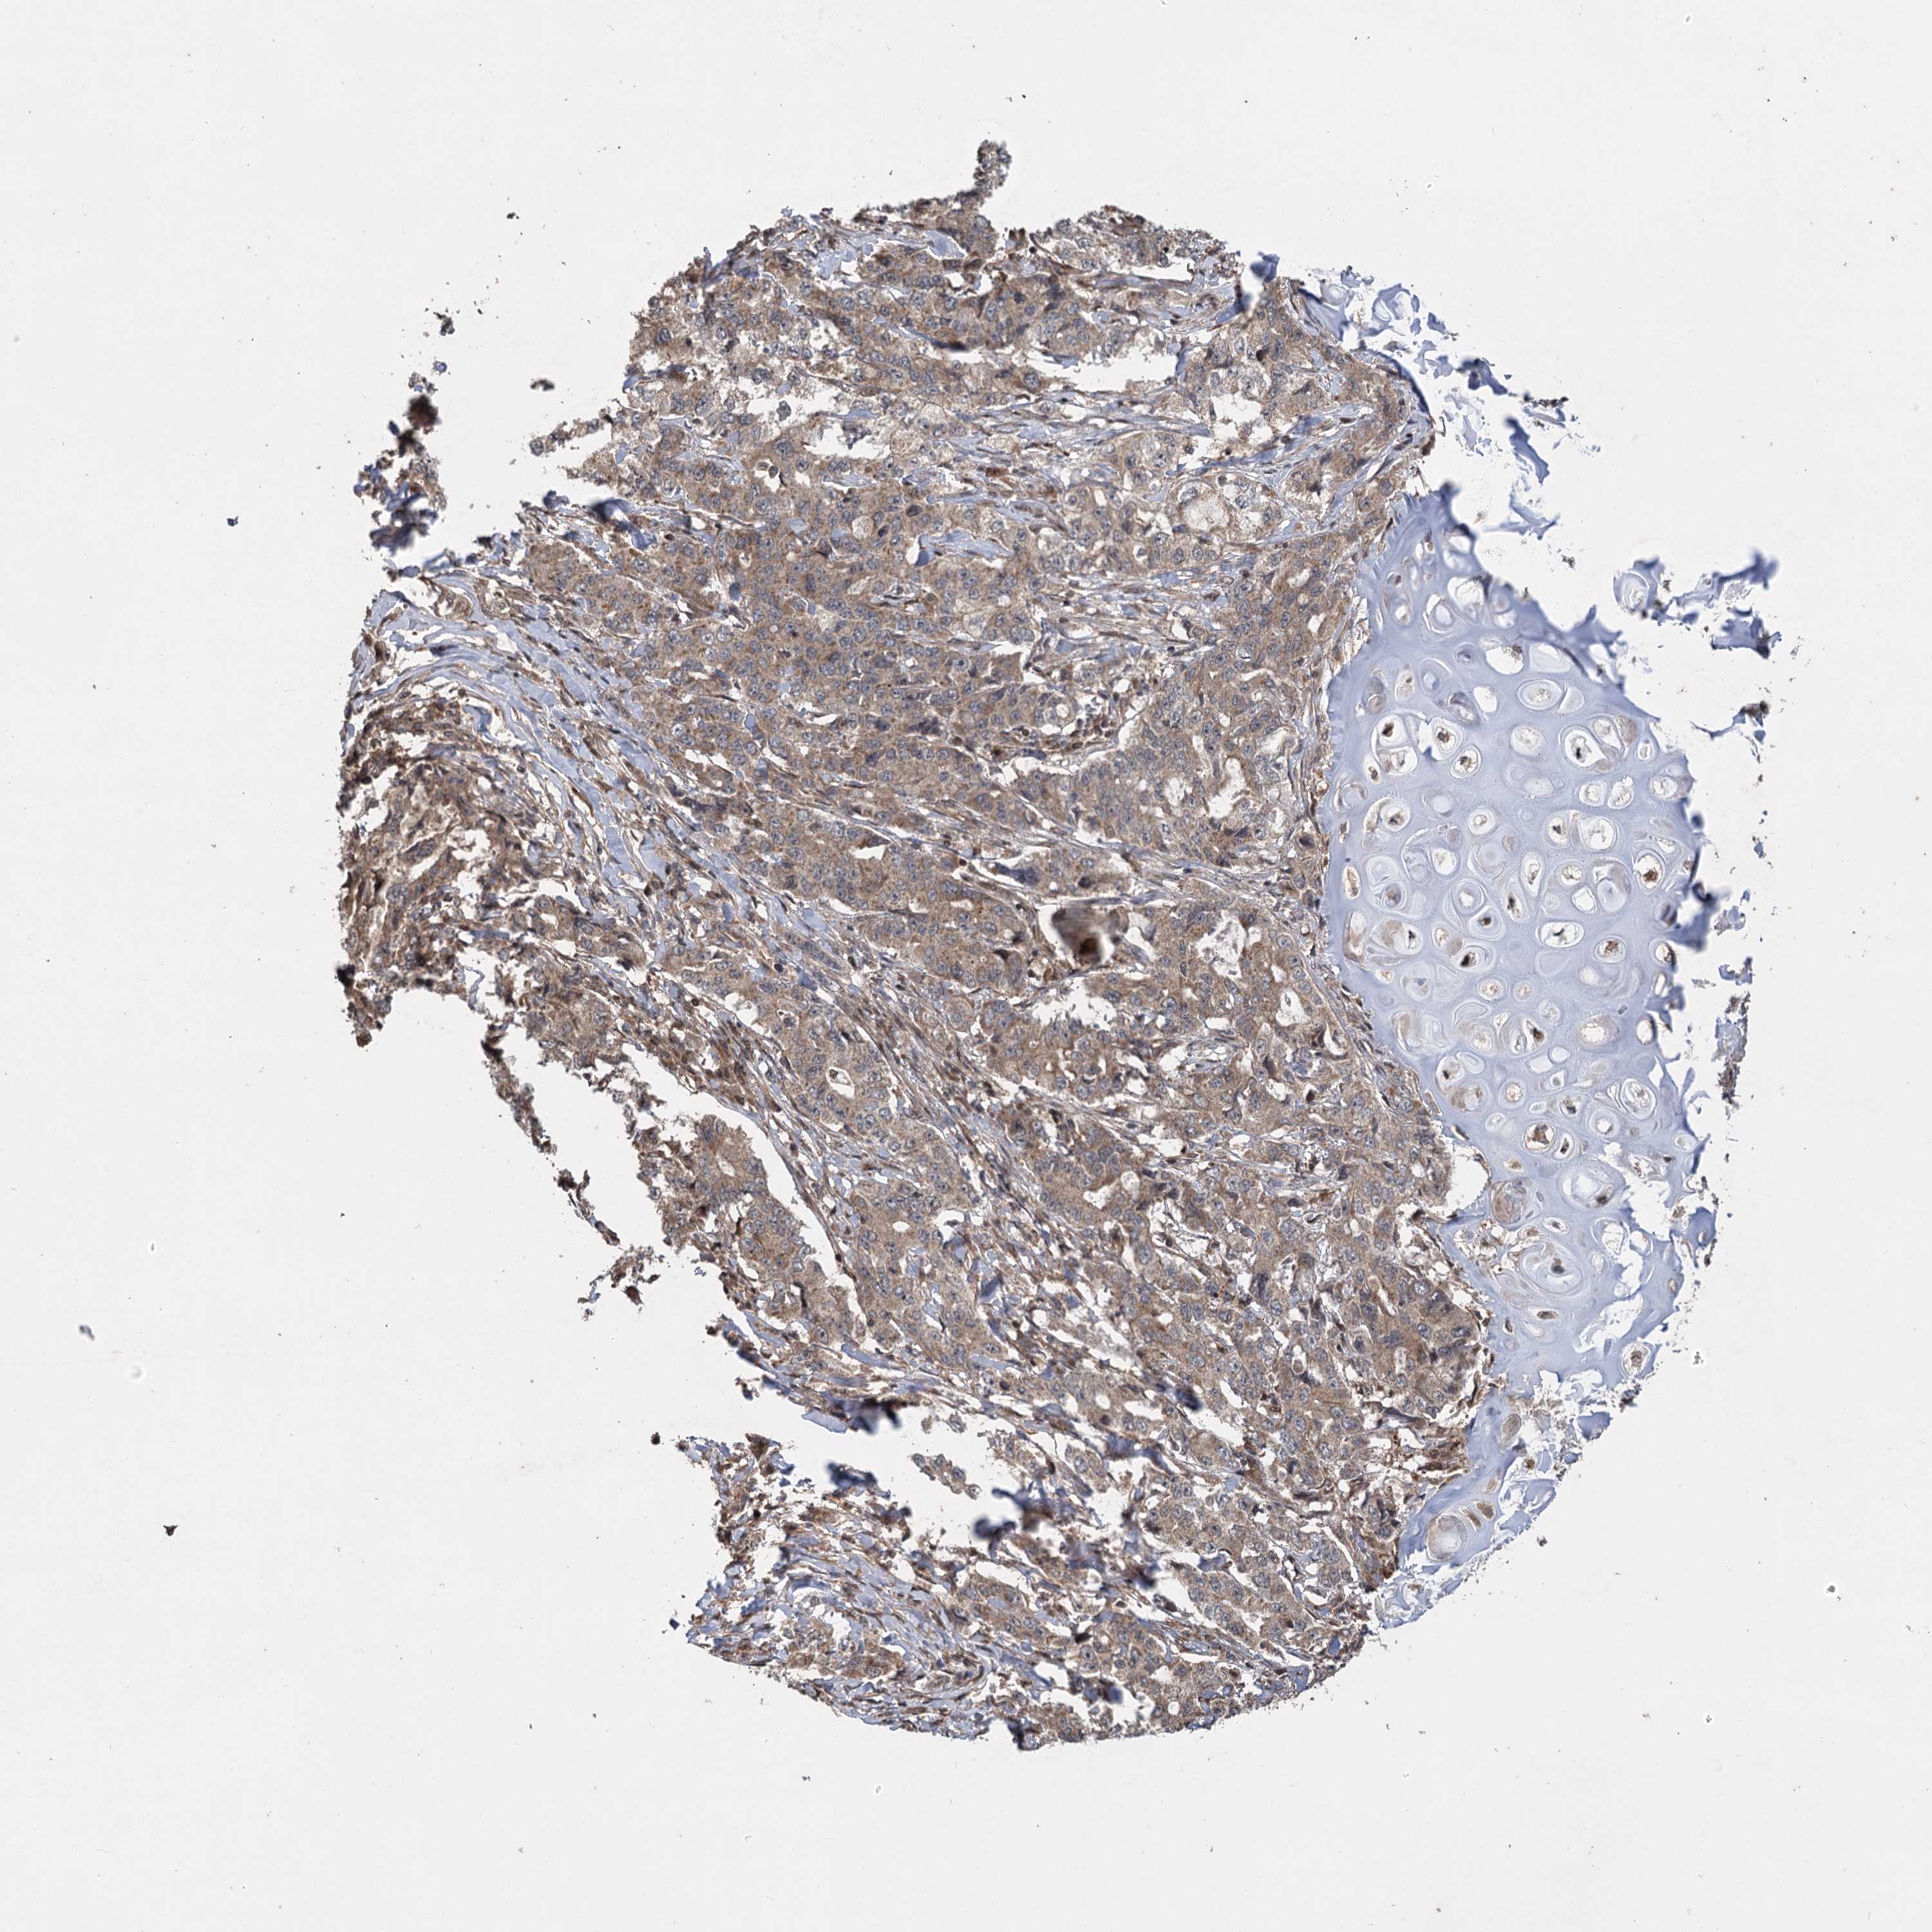

LUNG SQUAMOUS CELL CARCINOMA (TCGA) - Interactive survival scatter ploti

The Survival Scatter plot shows the clinical status (i.e. dead or alive) for all individuals in the patient cohort, based on the same data that underlies the corresponding Kaplan-Meier plots. Patients that are alive at last time for follow-up are shown in blue and patients who have died during the study are shown in red.

The x-axis shows the expression levels (FPKM) of the investigated gene in the tumor tissue at the time of diagnosis. The y-axis shows the follow-up time after diagnosis (years). Both axes are complimented with kernel density curves demonstrating the data density over the axes. The top density plot shows the expression levels (FPKM) distribution among dead (red) and alive patients (blue). The right density plot shows the data density of the survived years of dead patients with high and low expression levels respectively, stratified using the cutoff indicated by the vertical dashed line through the Survival Scatter plot. This cutoff is automatically defined based on the FPKM cutoff that minimizes the p-score. The cutoff can be changed by dragging the vertical line or by entering a cutoff value in the square labeled "Current cut-off".

Under the Survival Scatter plot the p-score landscape (black curve; left axis) is shown together with dead median separation (red curve; right axis). Dead median separation is the difference in median mRNA expression between patients who have died with high and low expression, respectively. It is calculated as follows: median FPKM expression of dead patients with high expression - median FPKM expression of dead patients with low expression. This is intended to aid the user in visually exploring custom cutoffs and the associated p-scores and dead median separation.

Individual patient data is displayed and can be filtered by clicking on one or more of the category buttons on the top of the page. Categories describing expression level and patient information include: high, low, alive, dead, female, male and tumor stages. The scale of the x-axis can be toggled between linear and log-scale by clicking on the "x log" button. Mouse-over function shows TCGA ID, patient information and mRNA expression (FPKM) for each patient.

& Survival analysisi

Kaplan-Meier plots summarize results from analysis of correlation between mRNA expression level and patient survival. Patients were divided based on level of expression into one of the two groups "low" (under cut off) or "high" (over cut off). X-axis shows time for survival (years) and y-axis shows the probability of survival, where 1.0 corresponds to 100 percent.

INSIG2 is not prognostic in Lung Squamous Cell Carcinoma (TCGA)

Best expression cut offi

Based on the FPKM value of each gene, patients were classified into two groups and association between prognosis (survival) and gene expression (FPKM) was examined. The best expression cut-off refers the FPKM value that yields maximal difference with regard to survival between the two groups at the lowest log-rank P-value. Best expression cut-off was selected based on survival analysis .

When clicking on this number, the vertical dashed line indicating cut-off, the interactive survival plot, and the Kaplan-Meier curve will be adjusted to show results based on the best expression cut-off.

: 7.95

P scorei

Log-rank P value for Kaplan-Meier plot showing results from analysis of correlation between mRNA expression level and patient survival.

N/A

Average pTPM 7.9

Number of samples 489